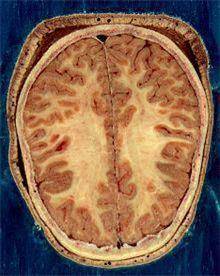

![뇌의 백질과 회색질 [출처: 위키 백과]](https://img2.daumcdn.net/thumb/R658x0.q70/?fname=https://t1.daumcdn.net/news/202401/24/yonhap/20240124090607765cqgm.jpg)

대뇌는 신경세포로 구성된 겉 부분인 회색질과 신경세포들을 서로 연결하는 신경 섬유망이 깔린 속 부분인 백질(white matter)로 이뤄져 있다. 피질은 회색을 띠고 있어 회색질, 수질은 하얀색을 띠고 있어 백질이라고 불린다.